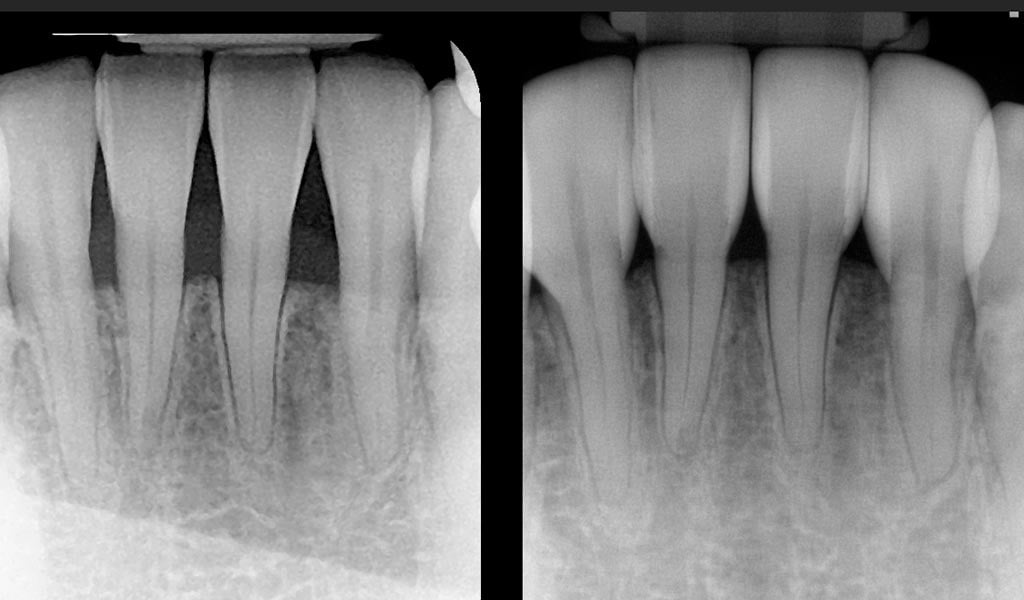

From doctorsaylor.com

New Treatment for Black Triangles between Teeth Saylor Dentistry Treatment For Black Triangles Web when it comes to treating black triangles between teeth, there are several different options. Reviewing the clinical options, the reasonable choices are papilla reconstruction for limited areas or. We explain what these dark triangles mean, how to treat. Web treatment of black triangles often requires an interdisciplinary approach, involving of periodontal; Web what can we do? Web treatment for. Treatment For Black Triangles.